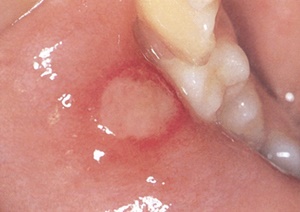

✅ 구내염은 입 안의 점막에 생기는 염증성 질환으로, 주로 궤양이나 붉은 반점의 형태로 나타납니다. 구내염은 다음과 같은 다양한 원인으로 발생할 수 있습니다:

증상

- 입안의 통증 및 불편감

- 붉은 반점이나 하얀 궤양

구내염의 증상은 매우 다양하며, 통증의 정도도 사람마다 다를 수 있습니다. 초기에는 작은 붉은 반점으로 시작되어 점점 커지면서 궤양으로 발전하는 경우가 많습니다.